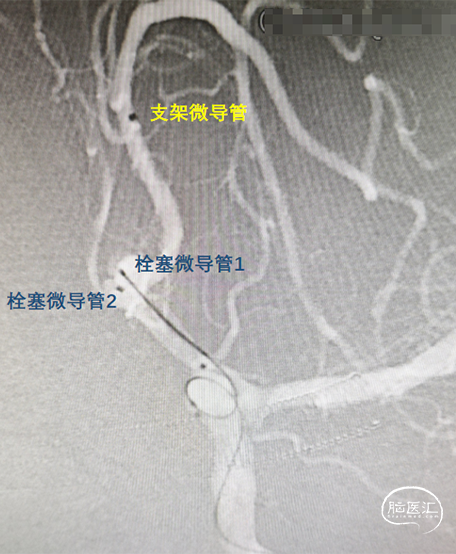

瘤颈较宽、多分叶,单支架辅助弹簧圈栓塞时,可能无法完全保护,易发生跑圈或无法稳定成篮,选择多支架植入(Y形)。

遂选择具有优异血管顺应性的编织型支架,植入后能够保留治疗通路,未来远端血管发生病变时仍能够通过介入方式进行治疗,同时高金属覆盖率有利于瘤颈修复,还能避免使用小圈栓塞小分叶瘤体时跑圈。

②瘤体多分叶,采用双系统填圈;

③微导管到位后在同侧优先释放一枚支架,缩窄瘤颈后填圈,再行穿网孔释放另一枚支架;

同侧释放一枚LEO Baby支架 2.5*18mm。

在右侧大脑前释放一枚LEO Baby支架 2.5*12mm,“Y”成型;

通过微导管2置入一枚1.5*2mm 弹簧圈后出现踢管;

造影见对侧大脑前血流恢复,远端瘤体已致密栓塞,但近端瘤体存在残留;

由于使用的为编织型支架,故结束手术不再填圈。